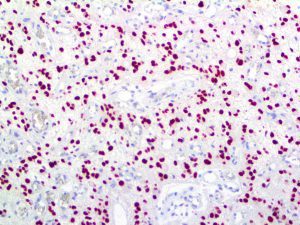

It is the ICU physician who is most likely to witness one of the deadliest manifestations of the abnormal immunological response, the cytokine storm syndrome (CSS). This response is also referred to by some as the cytokine release syndrome (CRS). CSS is characterized by continuous activation and expansion of macrophage and lymphocyte populations, which secrete large amounts of cytokines, causing the cytokine storm. This massive cytokine release is akin to hemophagocytic lymphohistiocytosis (HLH) disease, a syndrome characterized by initial unchecked and persistent activation of cytotoxic T lymphocytes and NK cells.

Clinical and laboratory manifestations of HLH include fever, enlarged liver and/or spleen, neurologic dysfunction, coagulopathy, liver dysfunction, cytopenias (i.e., low levels of erythrocytes, leukocytes, and/or platelets), hypertriglyceridemia, hyperferritinemia, hemophagocytosis, and eventually diminished NK cell activity as the immune system becomes progressively paralyzed. HLH can be familial (primary HLH) or secondary to another disease process (sHLH), such as rheumatic disease, in which it is referred to as macrophage activation syndrome (MAS, characterized by elevated ferritin).